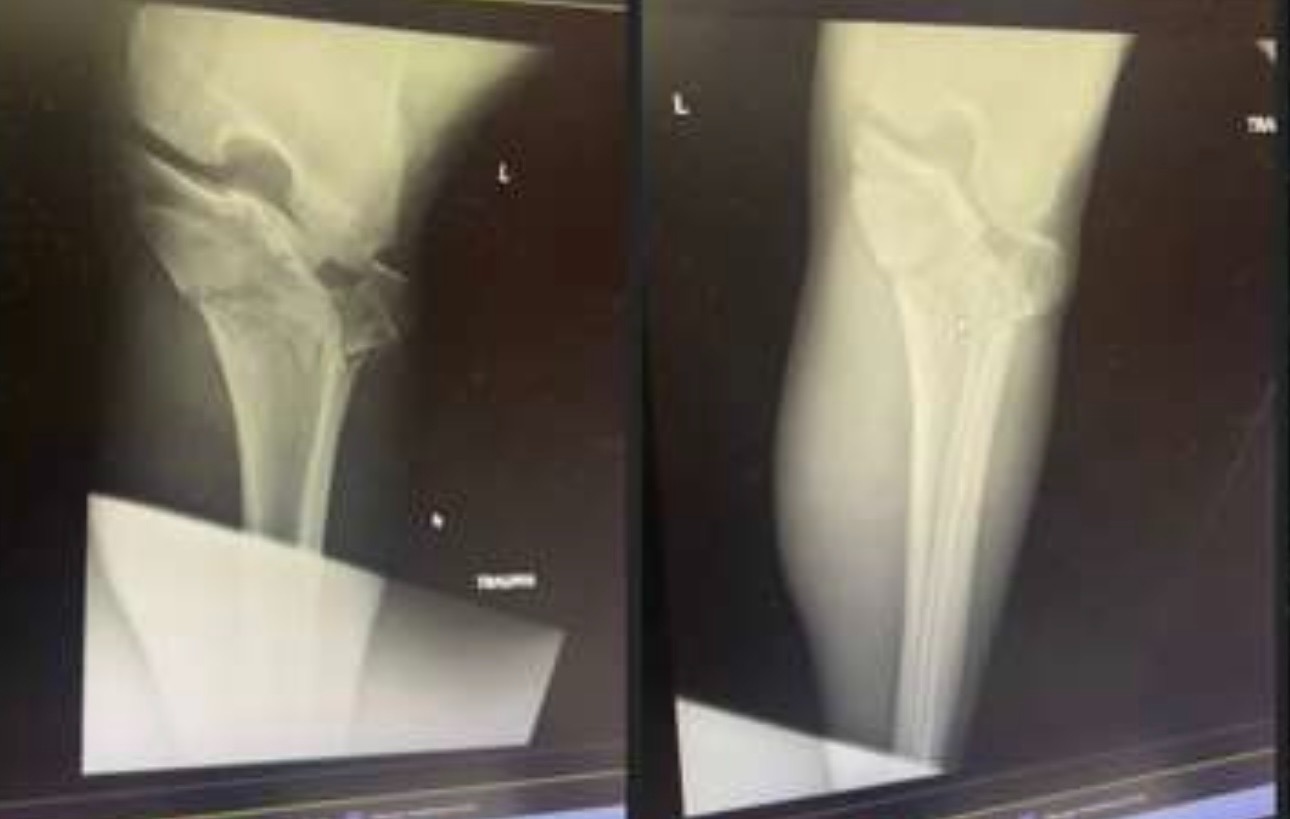

As most of you know, during Monday night's game our beloved Rat, Jon Gruber, took a very nasty fall and hurt his knee pretty badly. He had multiple Tibia Plateau fractures, and has already had one surgery for an external fixation. A second surgery is upcoming to put plates and screws in, in about 7-10 days once the swelling goes down.